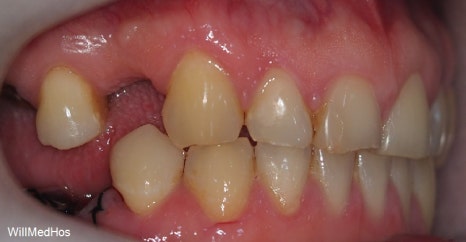

먼저 초진 구강 사진부터 보도록 하겠습니다.

▶초진 구강 사진

▲ 초진구강사진

충치로 인하여 뿌리만 남아있는 치아들과 심지어 자연 발치된 치아도 확인해 볼 수 있습니다.